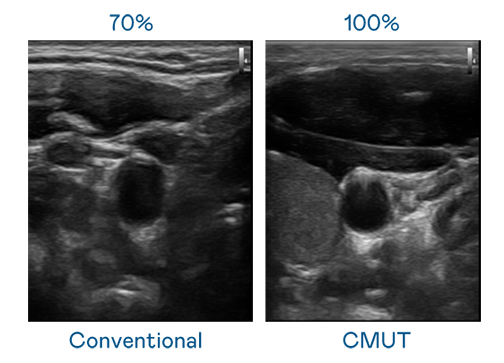

CMUT 技术是一种用电容式微机电元件来产生超音波讯号的技术。与传统 PZT 压电式技术相比,CMUT 频宽增加 30%,更宽频的超音波讯号让影像解析度大幅提升,是实现高影像品质医疗超音波扫描、促进精准医疗发展的关键技术。

大频宽带来超清晰影像

超音波影像的解析度高低,首先取决于探头能发出的讯号频宽。利来 CMUT 可提供高清晰的超音波讯号,提供高频宽、高灵敏度、影像纹理细节更高的超音波影像,协助医护人员缩短影像判读时间及利用精准的医疗影像进行诊断。